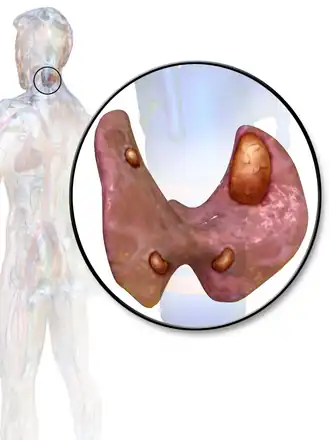

Um ser humano normalmente tem quatro glândulas paratireoides, localizadas por atrás da tireóide, no pescoço. A paratireoide secreta hormônio da paratireóide (PTH), que aumenta a concentração de cálcio no sangue (calcemia), ao induzir a liberação de cálcio dos ossos para o sangue e ao induzir os rins a reabsorverem o cálcio para evitar sua excreção. Quando um adenoma de paratireoide causa hiperparatiroidismo, mais hormônio da paratireóide é secretada, causando uma concentração elevada de cálcio no sangue (hipercalcemia).[2]

A cirurgia para remover o tumor é bem-sucedida em cerca de 95% do tempo. Paratiroidectomia é a remoção cirúrgica das glândulas afetadas, que agora podem ser executadas com uma técnica minimamente invasiva, com ajuda de exames de imagem para identificar a localização do tumor. Técnicas minimamente invasivas incluem procedimentos com menor abertura, guiados por rádio e vídeo-assistidas e cirurgia endoscópica.

Antes da cirurgia o tumor deve ser localizado. Apesar das glândulas paratireoides estarem normalmente localizadas atrás das tireoides, algumas pessoas têm uma ou mais glândulas paratireoides, em outros lugares do pescoço ou no peito. Cerca de 10% dos adenomas de paratireoide são ectópicos.[6] Portanto diversas técnicas de imagem são utilizadas, tais como o sestamibi, SPECT, ultra-som, ressonância magnética, e TC.[7].